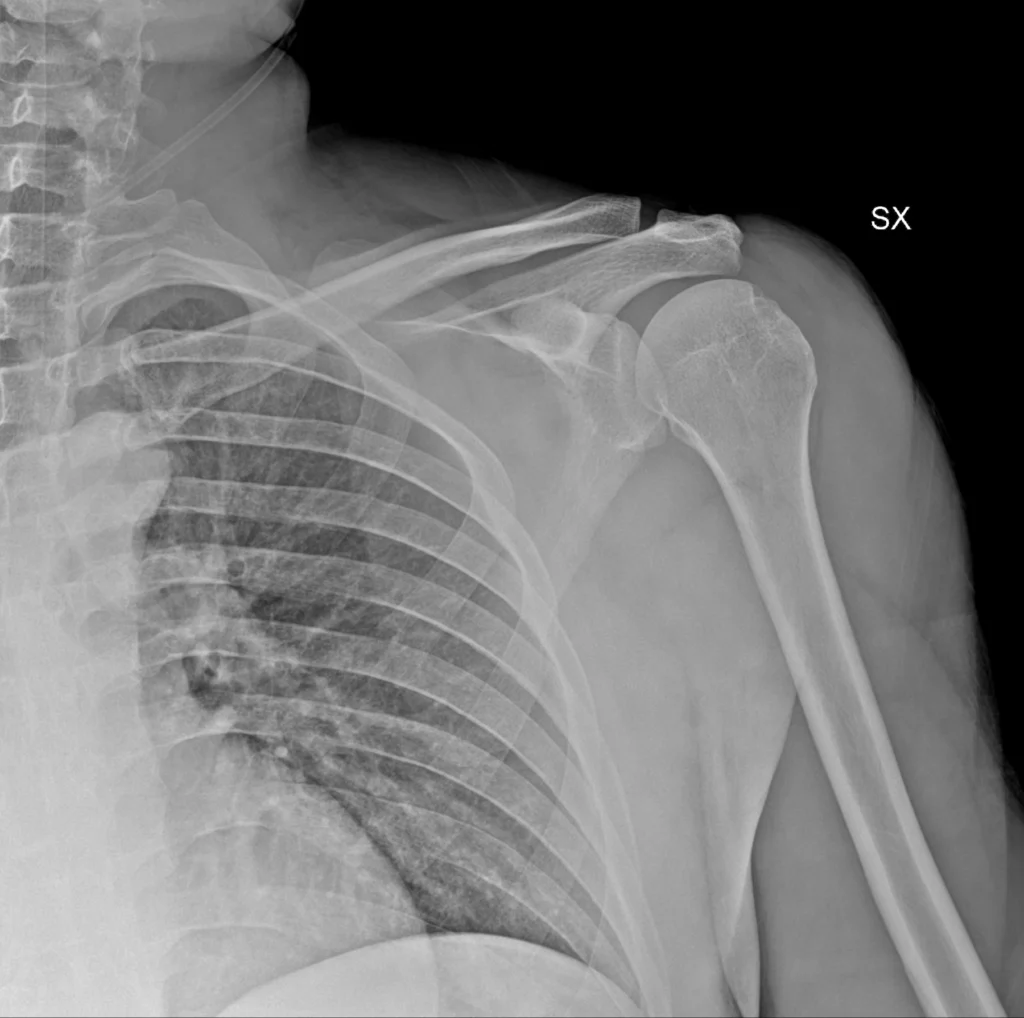

Luxación glenohumeral anterior

Consulta por dolor intenso y deformidad del hombro tras traumatismo. Incapacidad para movilizar el miembro superior.

Radiografia de hombro izquierdo, proyecciones AP. La cabeza humeral está descentrada respecto a la glenoides, con desplazamiento anteroinferior (la forma exacta puede variar según proyección). Esto es el dato esencial: no hay congruencia glenohumeral.